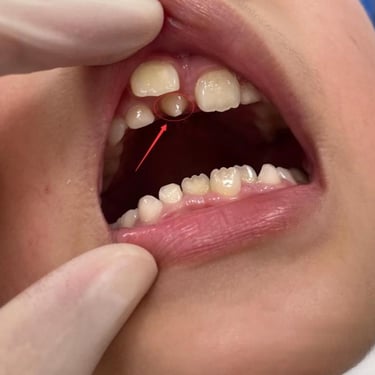

Absceso facial

Un absceso facial es una acumulación de pus en los tejidos faciales debido a una infección bacteriana.

Los pacientes pueden notar hinchazón, dolor intenso, fiebre y enrojecimiento en el área afectada.

El tratamiento incluye el drenaje quirúrgico del absceso y el uso de antibióticos para combatir la infección.